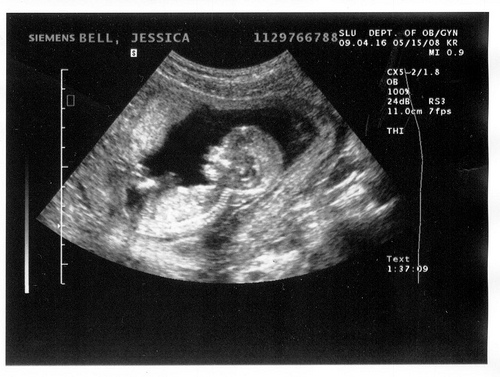

До 12 недель беременности на учет нужно стать еще и потому, что именно теперь врач может по УЗИ довольно точно определить возраст плода и примерную дату предстоящих родов.

Он чувствует вкус пищи, которую ест мама. У плода формируются свои вкусовые пристрастия. До 12 недель плод обладал мягким позвоночником. Теперь хрящи превращаются в косточки: формируется нормальный скелет. Между пальцев исчезают перепонки. Плод все больше становится похож на младенца. На УЗИ уже можно увидеть, кто это: мальчик или девочка.

УЗИ на 12 неделе беременности